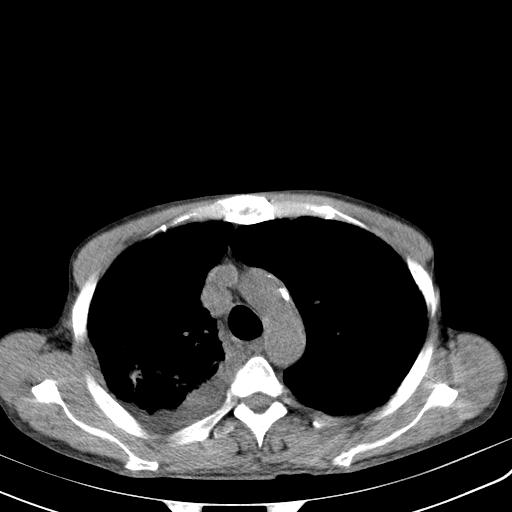

男性 75  咳嗽 一周前发热最高达39

右肺继发型tb并右侧tb性胸腔炎,右侧胸腔大量积液并右下肺膨胀不全,慢支肺气肿、多发肺大泡。建议抽胸水实验室检查并复查排除恶性在占位。

右上肺继发型肺结核,右胸腔中等量积液。

左上肺大泡。

结核的基础上有纵隔淋巴结肿大,右侧有胸水,但右侧纵隔反而窄,说明有肺有不张。

再就是右下肺有块影,和不张混合,还是不能除外肺癌。

1)右肺继发型肺结核。2)左肺胸膜下多发性肺大泡。3)右侧胸腔积液。